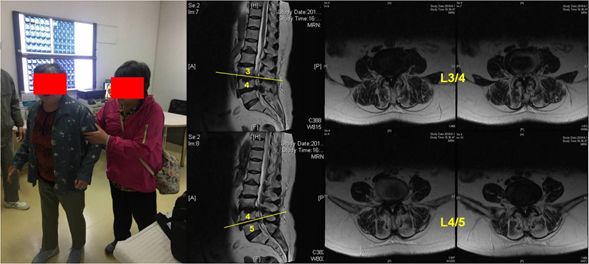

王阿姨门诊及腰椎核磁共振片

但因王阿姨年龄大、基础疾病多、影像学上提示椎管狭窄非常严重,多家医院以手术风险大、难度高建议保守治疗,濒临绝望的王阿姨联系上了多年生活在大陆的妹妹,妹妹辗转比较最终定带王阿姨前往海军军医大学附属长海医院进一步治疗。